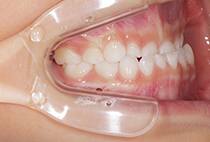

20代女性の患者さま。

八重歯の見た目が気になってご来院されましたが、実は顎の痛みや開口障害など、顎関節症の症状もありました。

そのため、かみ合わせと顎関節症の治療を同時に行ったにもかかわらず、2年間で治療が終了。

かみ合わせが整い咬筋の過緊張も改善しました。咬筋の肥大も治ってフェイスラインがすっきりしました。

最終的には美しい歯並びと、安定した痛みのないかみ合わせが実現しました。

しっかり前歯を下げるために、インプラントアンカーを使用してコントロールしました。

かみ合わせが整うと咬筋の過緊張が改善。

過緊張による筋肉肥大も改善しフェイスラインもすっきりしました。